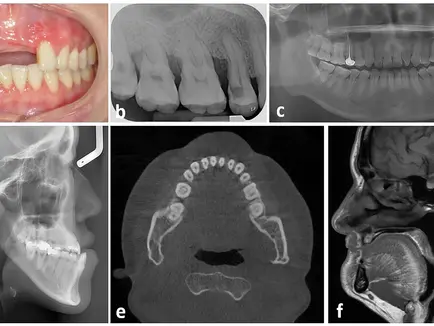

In the edentulous maxilla, progressive bone resorption often results in an acquired Class III

malocclusion, complicating prosthetic rehabilitation and implant positioning. The teeth-first

approach addresses this challenge by first placing dental implants to define occlusion. This framework then serves as a reference for subsequent orthognathic surgery. This sequence emphasizes three-dimensional planning and facilitates rehabilitation in complex atrophic

maxilla cases.